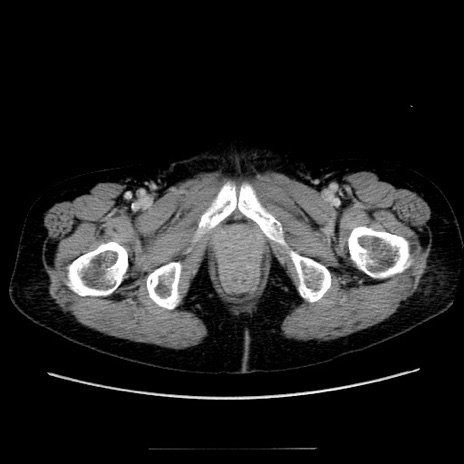

症例5(横断像)

【症例】70歳代女性

【主訴】お腹が張る

【現病歴】1週間くらい前から腹部膨満の自覚あり。昨日夜から増悪したため、本日救急外来受診。

【身体所見】意識清明、BT 36.5℃、BP 165/106mmHg、HR 80bpm、SpO2 98%、腹部:膨満、軟、自発痛・圧痛なし、触診にて不快感あり、腸蠕動音:減弱

【データ】WBC 12600、CRP 1.04